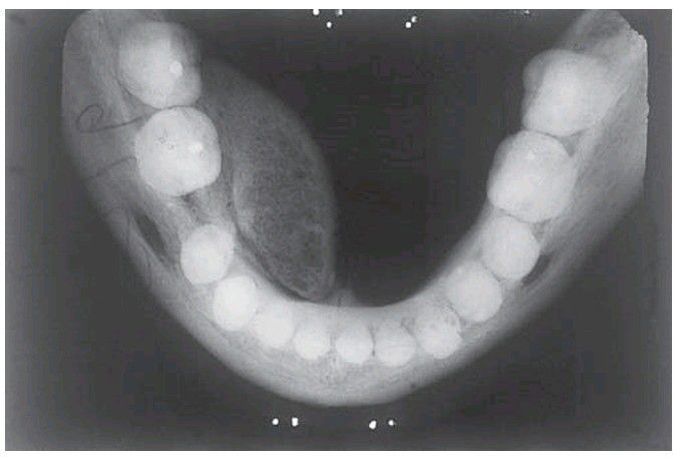

. The tumour has arisen from a relatively narrow base lingually to the molars but has been moulded forward during growth by pressure of the tongue. The trabecular pattern of cancellous bone can be seen. A torus mandibularis arises further forward on the jaw, arises from a broad base and is usually bilateral.